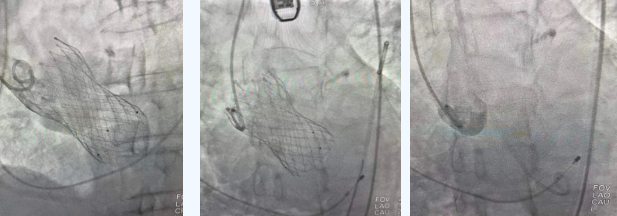

在麻醉手術(shù)中心的配合下,曾廣偉主任用導(dǎo)管經(jīng)股動脈鞘進(jìn)入主動脈瓣目標(biāo)位置,經(jīng)豬尾導(dǎo)管造影可見主動脈瓣大量返流,因左室流出道較寬,大于瓣膜落腳點(diǎn)直徑,瓣膜釋放位置選擇及釋放難度極大。更為關(guān)鍵的是,患者常規(guī)四個(gè)錨定點(diǎn)只有一個(gè)可以用,定位要極其精準(zhǔn)才能保證瓣膜釋放后牢靠,同時(shí)不能有大的殘余瘺!稍有移位可能就需要再次植入瓣中瓣或者開刀!

術(shù)中,曾廣偉主任團(tuán)隊(duì)高效配合,完成了特定時(shí)間點(diǎn)起搏心臟、臨時(shí)短時(shí)間關(guān)閉呼吸機(jī)、降低主動脈瓣阻力、快速釋放瓣膜等一系列高難度操作,有效保證瓣膜精準(zhǔn)釋放。瓣膜釋放經(jīng)TEE確認(rèn),主動脈瓣膜釋放位置佳,經(jīng)豬尾導(dǎo)管造影,主動脈瓣返流即刻消失,且無瓣周瘺。